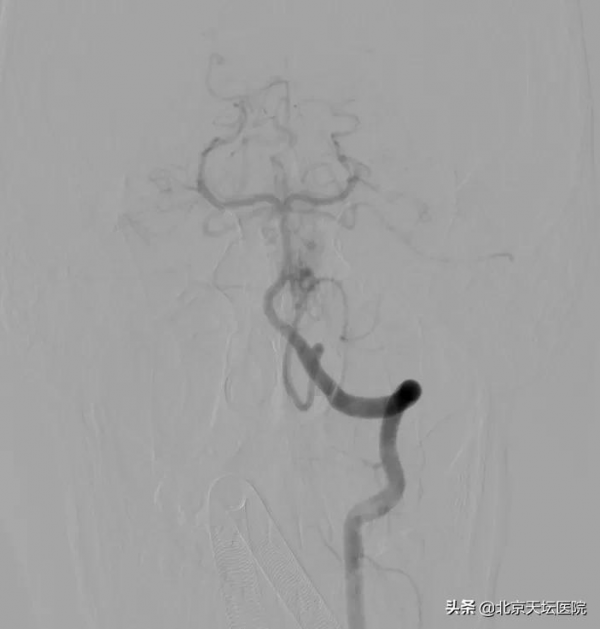

圖:雙側椎動脈造影見右側小腦上動脈、雙側小腦後下動脈向動靜脈畸形供血

“患者小腦蚓部都是雜亂的血管團,但由於血腫對動靜脈畸形顯影干擾很大,病灶的供血很可能比影像學檢查上能看到的複雜,手術難度很高。”陳曉霖說,綜合各方面判斷,小豪因動靜脈畸形導致出血的可能性比較大,由於他後顱窩出血量很大,隨著水腫的加重,很可能會壓迫腦幹或導致急性腦積水;同時,因為患者年齡只有17歲,將來再破裂出血的可能性很大,目前患者有手術指徵,透過複合手術可以完全治癒。

“複合手術室可以對手術患者進行血管造影檢查,根據造影檢查結果進行手術,並隨時可以造影檢視手術效果,不必再像以往那樣先做造影,再進手術室手術,然後再推出手術室做造影。” 陳曉霖介紹,小豪的全腦血管數字減影造影顯示,他的出血病灶是位於小腦蚓部的腦動靜脈畸形,而且右側小腦上動脈和雙側小腦後下動脈都參與了動靜脈畸形的供血,動脈極其迂曲,不論是栓塞前的微導管超選還是栓塞後的微導管撤出都存在一定難度。

根據造影結果,醫生們選擇對右側小腦上動脈和左側小腦後下動脈進行栓塞以降低術中出血風險。由於動脈迂曲、活動度極大,微導絲和微導管的每一寸進退都冒著刺破動脈的風險,足足用了一個小時,兩支目標動脈中病灶的供血分支和一部分病灶被成功栓塞,正常血管分支被完整保留。